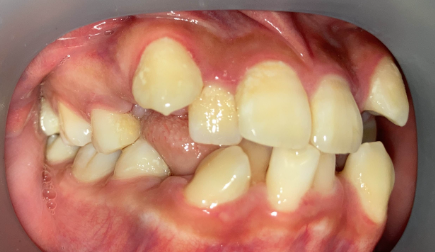

リカバリー症例の初診時の口腔内|奈良の矯正歯科

初診時

他院で非抜歯矯正を受けたものの、口元の突出感が改善せず来院。精密検査の結果、上下4本の抜歯が必要と判断し、ワイヤー矯正でやり直しました。